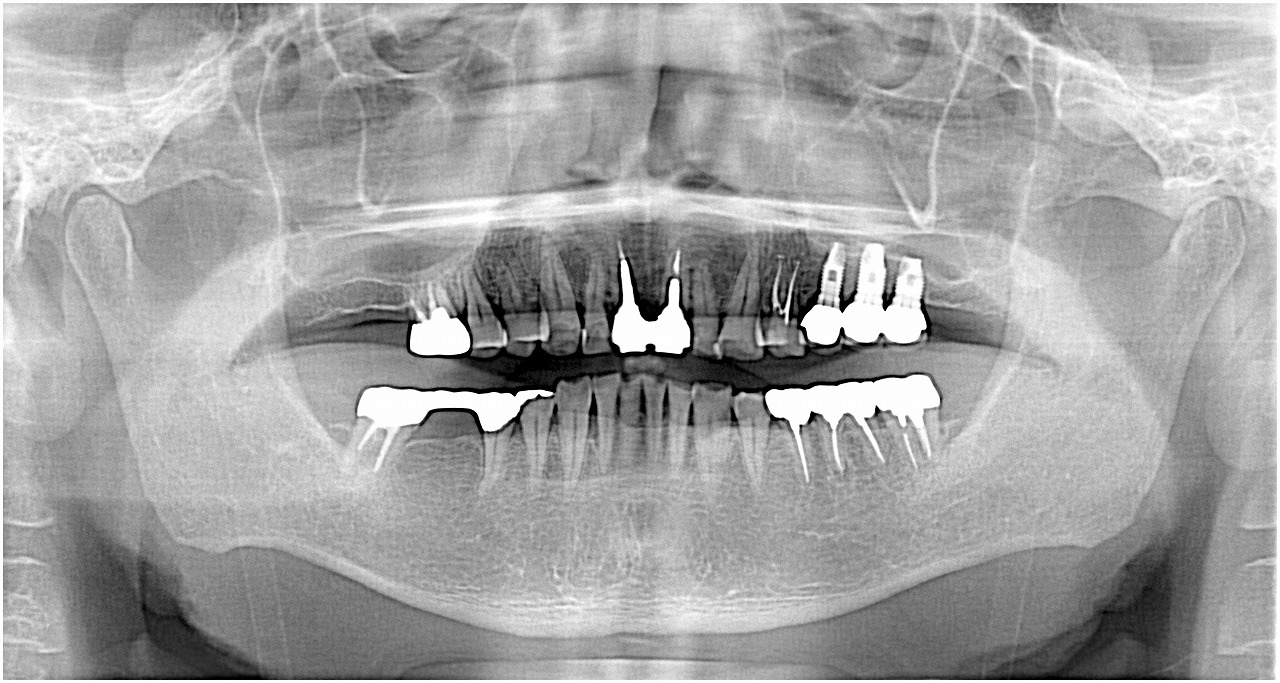

術後の機能時のパノラマになります